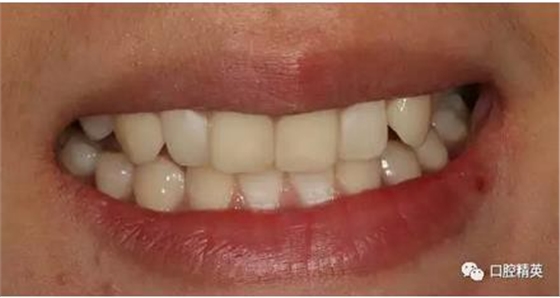

臨時(shí)冠修復(fù)

使用原始模翻制的臨時(shí)冠

術(shù)前,術(shù)中,術(shù)后對(duì)比